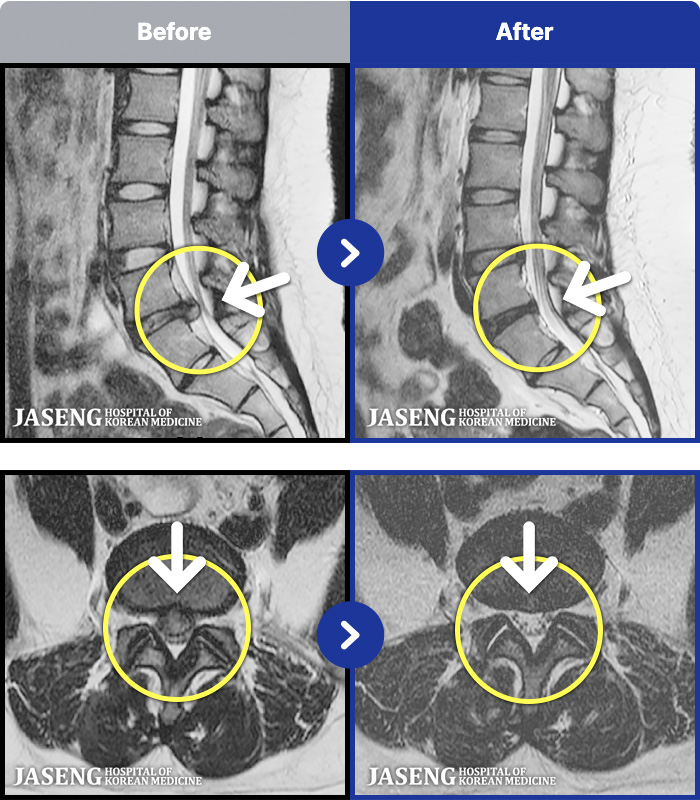

1,291 MRI ũ ʸ Ȯϼ.

[뱸] 19.11.28~25.05.06